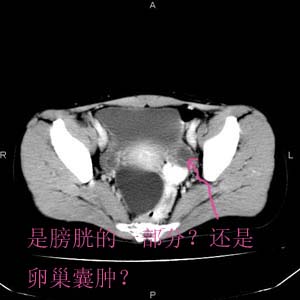

患者女性,39岁,下腹部不适2年,多次b超提示盆腔囊性占位(最大径约约6.1 cm),多考虑卵巢囊肿。一周前德国妇科专家来我院指导工作,欲行腹腔镜下切除,术中探查结果未发现病变,随用举宫器上抬子宫,观察双侧卵巢形态、大小如常!专家怀疑囊肿已破裂,术后行盆腔增强扫描,患者欲申请医疗事故鉴定。以下是增强后的图像:

想请各位老师分析,病变就ct显示,1.能否区分来源于腹膜外还是腹膜腔内?2.来源于卵巢还是其它部位?3.如何解释腹腔镜探查结果?

考虑 膀胱直肠见囊性占位病灶

楼主所指应该是膀胱的容积效应!另:盆腔内子宫 直肠隐窝囊性病灶-来源难定。建议手术切除!